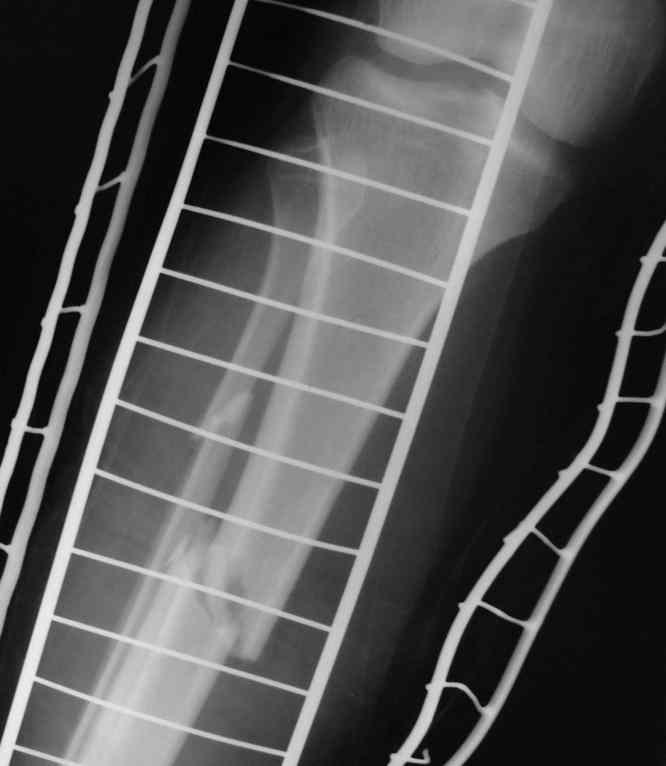

Здравствуйте, коллеги! 27/01/07 в отделение поступила девушка с множественным переломом костей таза справа с нарушением тазового кольца, ротационная нестабильность (седалищная, лонная кости, крыло подвздошной кости, перелом дна вертлужной впадины) и закрытый перелом обеих костей голени справа. При поступлении наложена система скелетного вытяжения за пяточную кость справа. Проведена противошоковая терапия. Состояние в данный момент стабильное. Планируется оперативное лечение перелома костей голени в наших условиях и наложение системы скелетного вытяжения за правое бедро на этой неделе. Просим рассмотреть вариант оперативного лечения травмы таза в условиях УНИИТО.